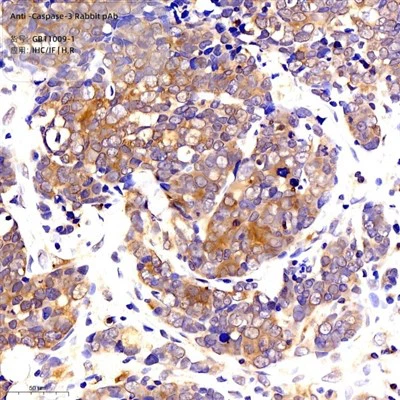

Upotetun rotta -sydämen immunohistokemia käyttämällä CD34 (GB 11013-1) laimennuksella 1: 300 (400x linssi) |

Upotetun rotta -munuaisen immunohistokemia käyttämällä CD34: tä (GB 11013-1) laimennuksella 1: 300 (400x linssi) |

Upotettujen hiiren maksan immunofluoresenssi käyttämällä CD34 (GB 11013-1) laimennuksella 1: 900 (400x linssi) |

Upotetun hiiren pernan immunofluoresenssi käyttämällä CD34: tä (GB 11013-1) laimennuksella 1: 900 (400x linssi) |

Upotettujen parafiinin upotetun rotan katkoksen immunofluoresenssi käyttämällä CD34 (GB 11013-1) laimennuksella 1: 900 (400x linssi) |